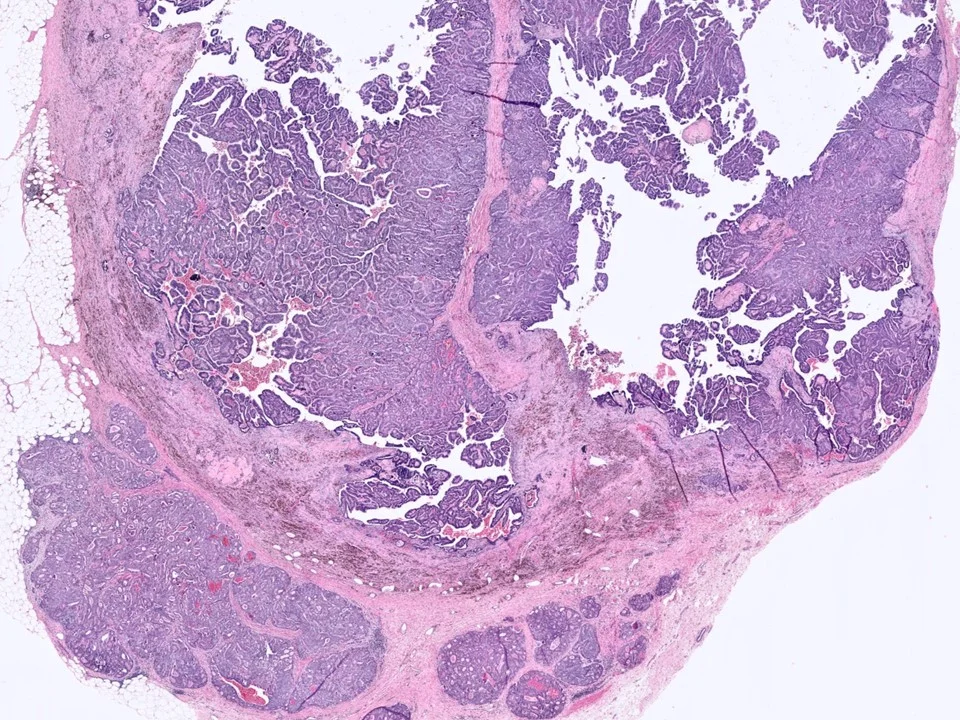

Malignant Phyllodes Tumor

Frond-like projections of cellular stroma covered by epithelium and myopeithelium protruding into epithelial-lined cystic spaces create a leaf-like appearance.

Malignant phyllodes have an infiltrative border (as pictured here), highly cellular stroma, stromal cells with moderate to marked nuclear pleomorphism, and prominent mitotic activity (>/= 10 mits per 10 HPF)